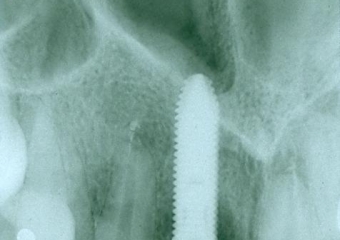

Raio X inicial